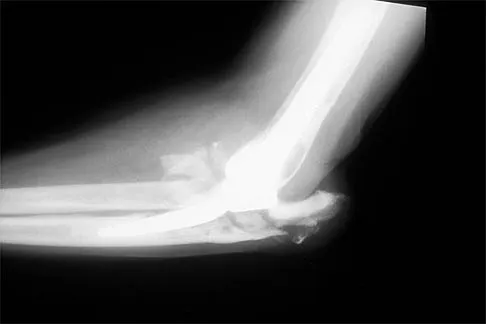

A 5-year-old boy sustained an elbow injury. Examination in the emergency department reveals that he is unable to flex the interphalangeal joint of his thumb and the distal interphalangeal joint of his index finger. The radial pulse is palpable at the wrist, and sensation is normal throughout the hand. Radiographs are shown in Figures 6a and 6b. In addition to reduction and pinning of the fracture, initial treatment should include

Explanation

The findings are consistent with a neurapraxia of the anterior interosseous branch of the median nerve. This is the most common nerve palsy seen with supracondylar humerus fractures, followed closely by radial nerve palsy. Nearly all cases of neurapraxia following supracondylar humerus fractures resolve spontaneously, and therefore, further diagnostic studies and surgery are not indicated. Cramer KE, Green NE, Devito DP: Incidence of anterior interosseous nerve palsy in supracondylar humerus fractures in children. J Pediatr Orthop 1993;13:502-505.